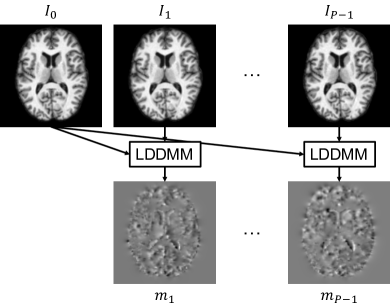

In this paper, we address the problem of predicting follow-up image scans of a specific subject with a baseline scan as input, using a deep neural network learned from longitudinal data with missing scans. To learn a growth trend for a specific subject from a population and to overcome DNNs’ blurry prediction issue for the follow-up scans, we integrate image registration techniques used in image regression models with a mixed CNN and RNN architecture, as shown in Fig. 1. Instead of directly working on input images to predict image sequence of a subject, our model predicts a sequence of vector momenta (Singh et al., 2013) for a baseline image input. These vector momenta are associated with their baseline image and parameterize deformation mappings between images under the LDDMM framework. We use the predicted vector momenta to deform the baseline image to different time points and generate the corresponding image sequence. We train our predictive image regression network by using the first image of a subject and its associated vector momentum sequence for each image scan, which is generated using LDDMM image registration. To handle the missing data, we introduce a binary mask into the training procedure, which ignores the loss calculation for predictions at missing time points. During the prediction procedure, given an individual with one image scan, our model can predict how it changes over time according to the learned population trend.

In this section, we present the architecture of our predictive image regression network (Fig. 1) in detail. Assume we have a population of images collected from subjects and each subject has a varying number () of images () scanned at different time points (). The objective of image regression is to uncover the relationship between images and their associated variable . Instead of directly performing regression on images, we leverage LDDMM and geodesic shooting with vector momentum (Singh et al., 2013; Vialard et al., 2012) to convert the longitudinal images of a subject into an initial image and a sequence of associated momenta (Section 2.1). The relation of the initial image and its momentum sequence to their associated variables, like age, will be learned through training a deep neural network (Section 2.2). The predicted momentum sequence for an input image can shoot it forward to generate the corresponding image sequence (Section 2.3).

Given a sequence of longitudinal images from a subject , we select the first scan as the baseline image and compute the initial vector for each scan , by registering to using LDDMM, as shown in Fig.2. Note that the registration of the baseline image to itself is not shown in Fig. 2, since the resulting vector momentum is zero; but this zero momentum serves as a starting point for the recurrent network training and prediction in Section 2.2. Specifically, each vector momentum has , , and components and the dimension has zero momentum for a 2D image. As a result, we represent the image sequence of a subject as one image and its associate vector momentum sequence. Each vector momentum inherits the associated variable of its corresponding image. That is, we have a population of data represented as by using LDDMM and geodesic shooting.